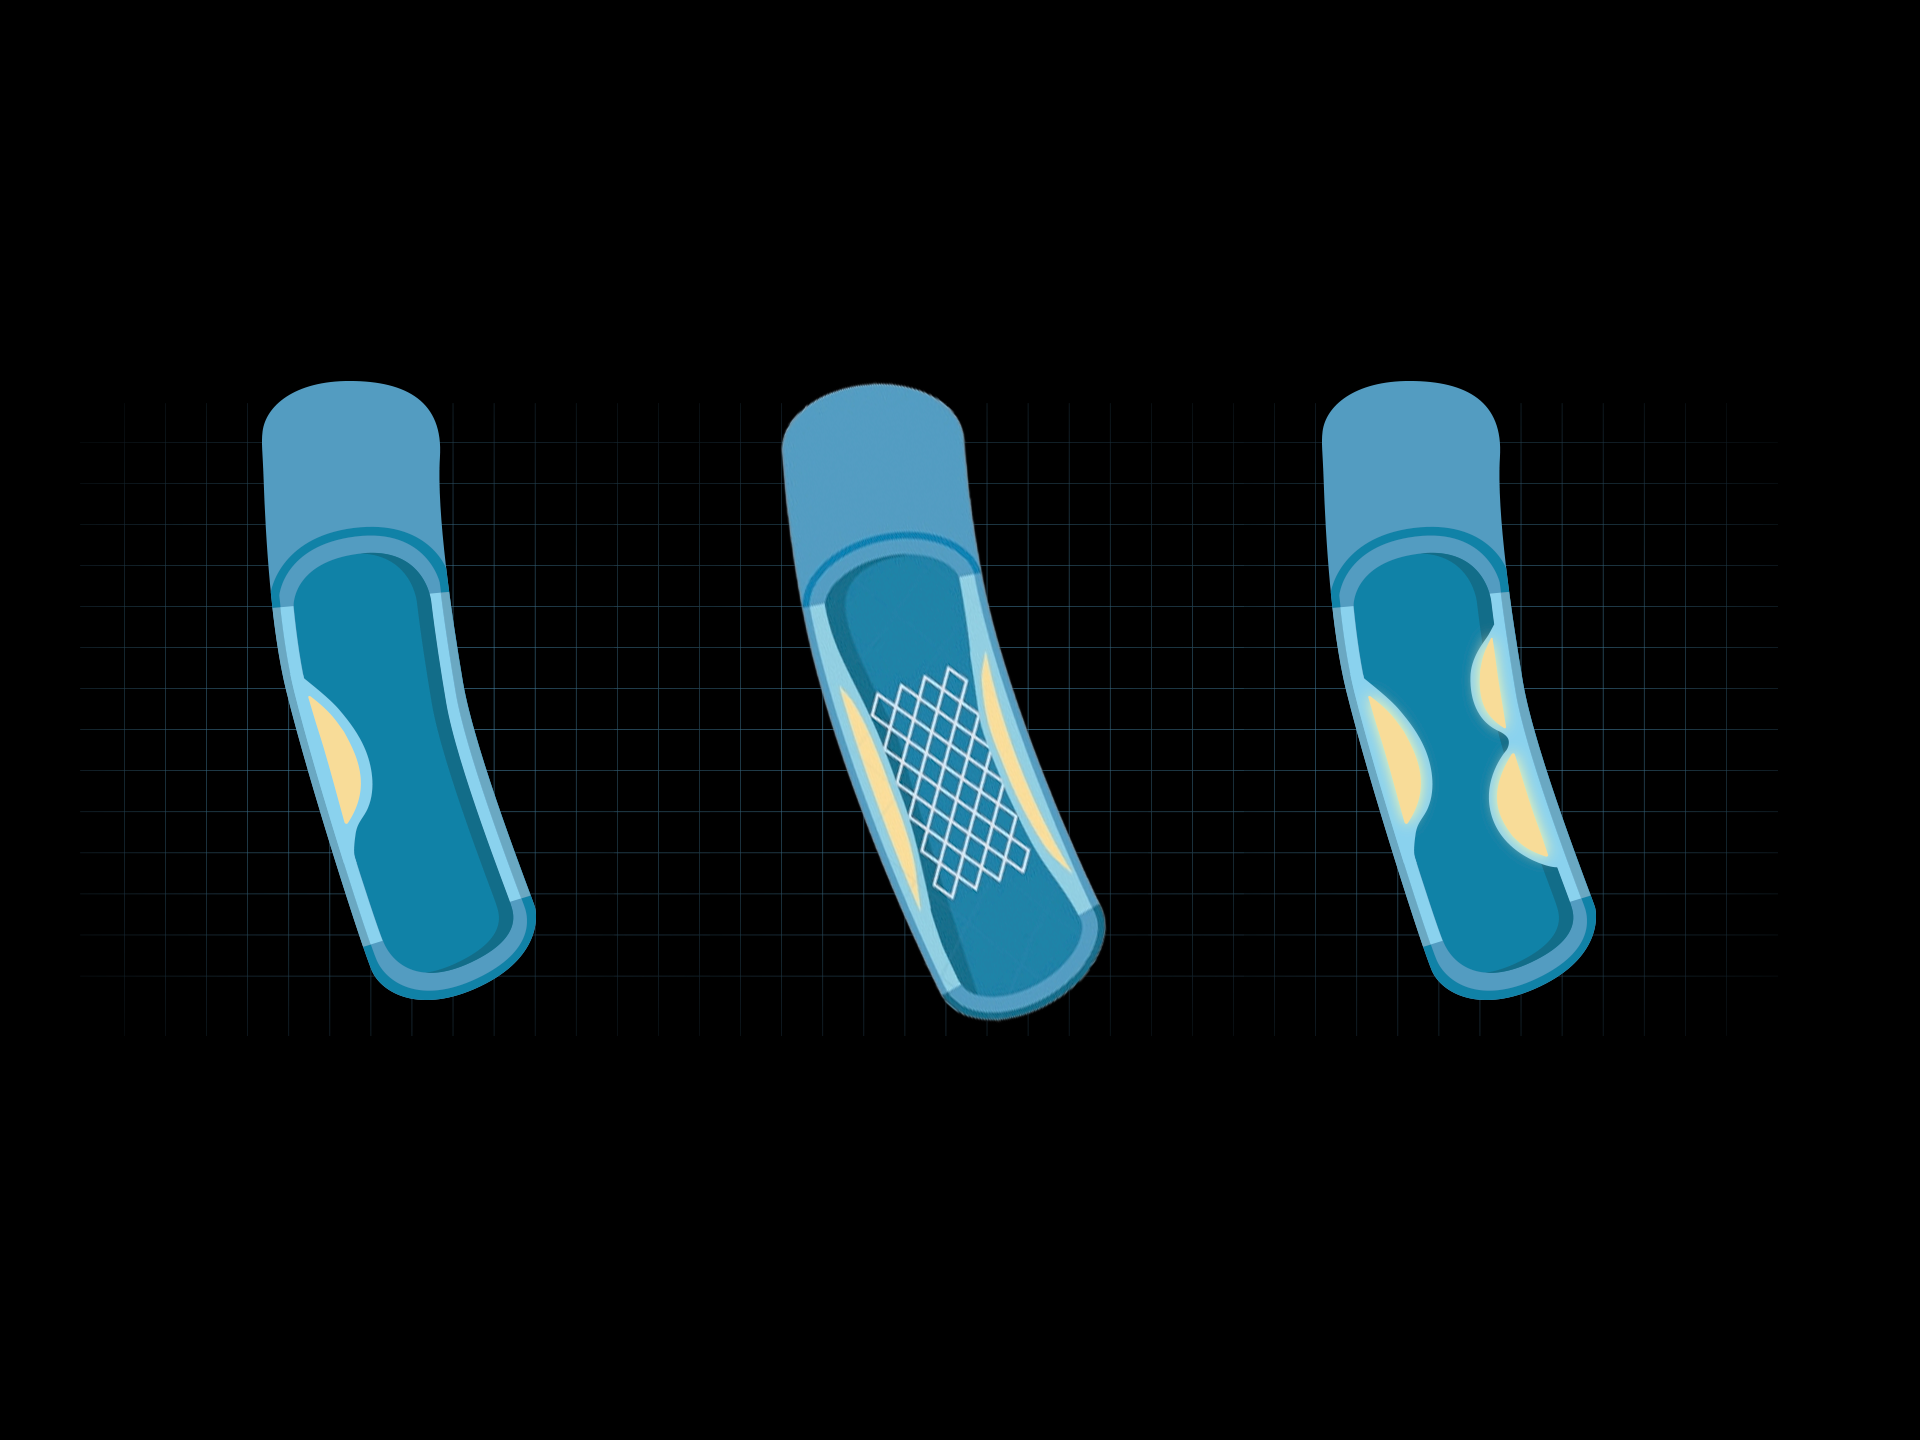

相同辐射剂量下

低对比度分辨率提升

相同辐射剂量下

空间分辨率提升

相同低对比度分辨率下

辐射剂量减少

相同辐射剂量条件下

图像噪声减少